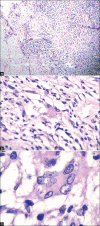

Disseminated histoplasmosis with oral and cutaneous manifestations

Histoplasmosis is a systemic mycotic infection caused by the dimorphic fungus, Histoplasma capsulatum. Systemic histoplasmosis has emerged as an important opportunistic infection in human immunodeficiency virus (HIV) patients and those in endemic areas. Reported cases of histoplasmosis have been low in India with less than 50 cases being reported. We are reporting a case of disseminated histoplasmosis with oral and cutaneous involvement in an HIV seronegative patient.